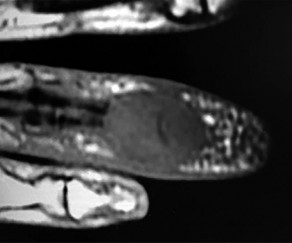

Question 3:

A 32-year-old woman presents with persistent knee pain. Imaging reveals an eccentric, lytic epiphyseal lesion extending to the subchondral bone, characteristic of a giant cell tumor of bone. She is prescribed denosumab prior to surgical intervention. What is the precise mechanism of action of this medication?

Correct Answer: Binds to RANK ligand (RANKL) preventing its interaction with the RANK receptor

Explanation:

Denosumab is a human monoclonal antibody that binds specifically to RANKL (Receptor Activator of Nuclear factor Kappa-B Ligand), a protein essential for the formation, function, and survival of osteoclasts. By neutralizing RANKL, denosumab prevents it from binding to the RANK receptor on osteoclast precursors, dramatically decreasing osteoclast-mediated bone destruction, which is the primary pathology in Giant Cell Tumor of Bone.